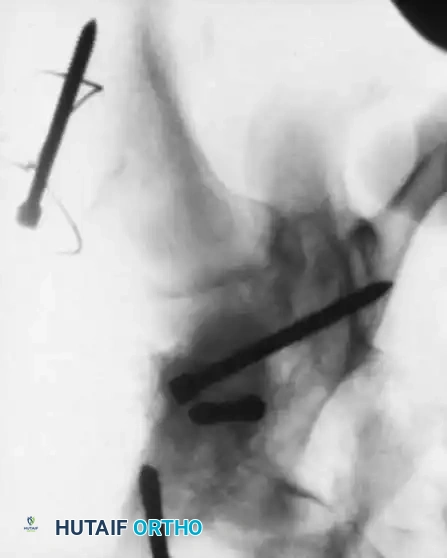

- Reduction: Closed reduction on a fracture table.

- Fixation: For "low" cervicotrochanteric fractures, simple screw fixation is often inadequate due to the lack of cortical support inferiorly.

- Technique: Utilize a pediatric dynamic hip screw (DHS) or a cannulated screw with an attached side plate. This converts shear forces into compressive forces and rigidly maintains the neck-shaft angle.

Fig. 15: Intraoperative reduction of the Type III fracture.

Fig. 16: Final fixation utilizing a cannulated screw and attached side plate to neutralize shear forces.